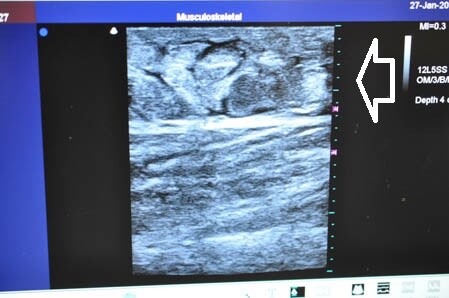

画像上しっかりと皮下脂肪は根こそがれており

間違いなく患者様のご期待にはそえられると思います。